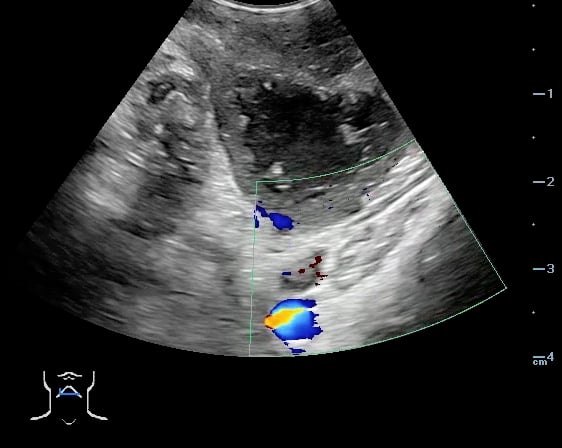

- The carotid artery is seen as an anechoic tubular structure along the posterolateral aspect of the tonsil on ultrasound. Its relationship to the abscess cavity should be determined. Color Doppler can help locate the carotid artery.

- Figure 47 and 48. PTA with color Doppler of carotid artery